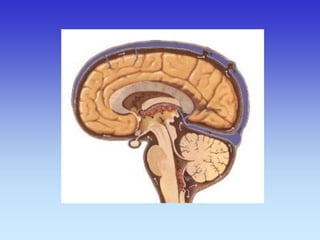

Sagitalni presjek

Koronarni presjek

Corpus callosum

Thalamus

Pons

Splenium of Corpus callosum